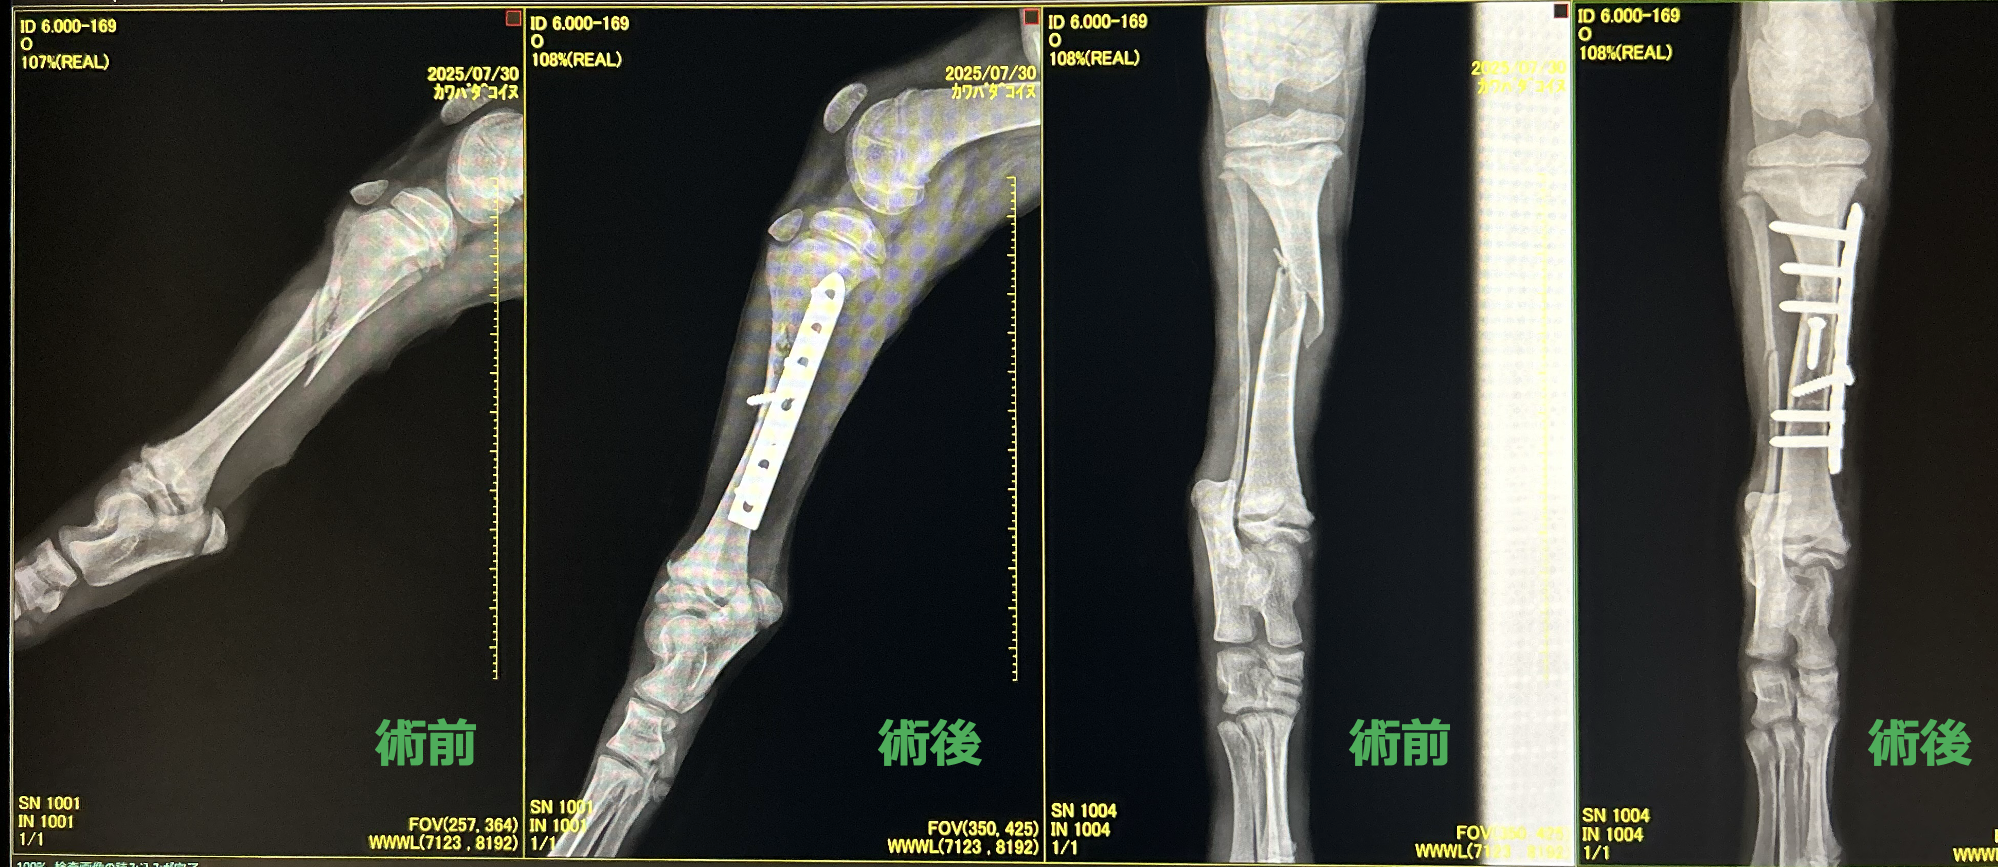

脛骨長斜骨折

犬の脛骨骨折は、後肢(すねの骨)が、外傷により折れる病気である。

犬種 コリー

年齢 2ヶ月齢

体重 5.2kg

レントゲン、CTより右脛骨の斜骨折または螺旋骨折が認められた

中和プレート固定、ラグスクリュー

before

after